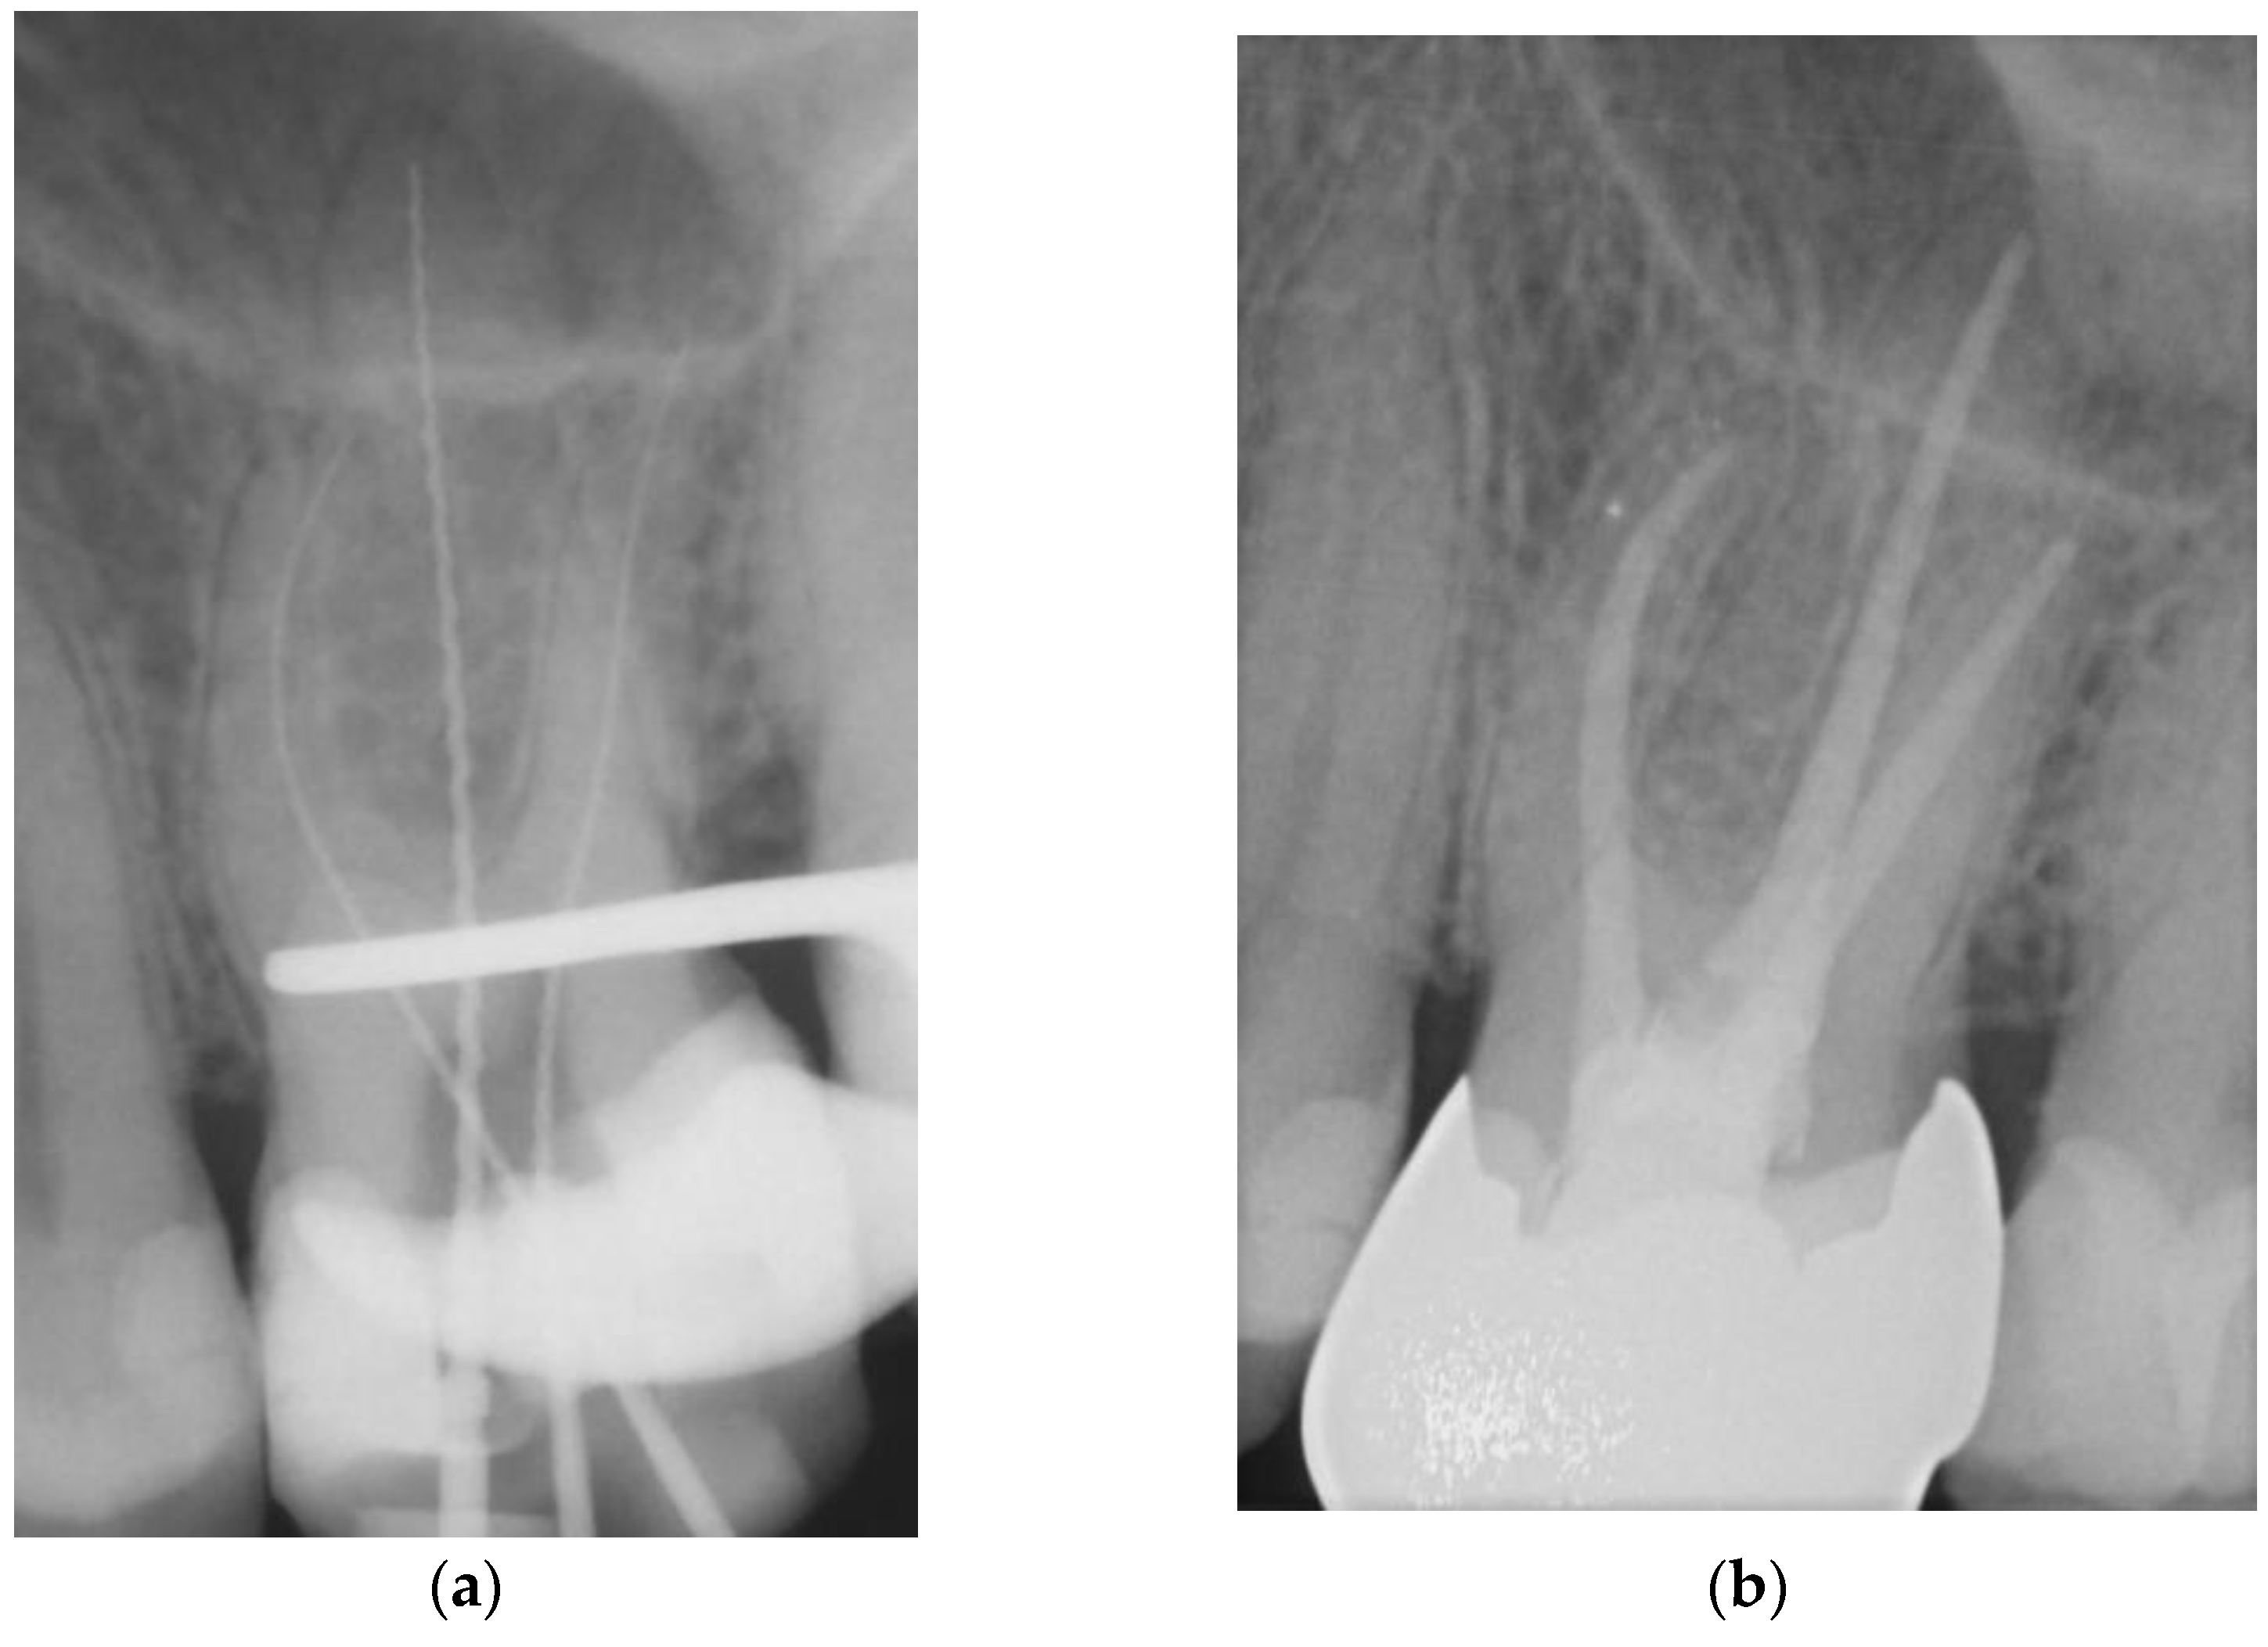

Figure 1. Representative example of root canal filling with Resilon® using the continuous wave of condensation technique (CWR); working length radiograph of tooth 36 (a); 6-year follow-up radiograph showing complete apical healing (b). - Matching-taper single-cone obturation with gutta-percha and the epoxy-resin-based sealer AH Plus® (SCGP) (Figure 2).

Figure 2. Representative example of root canal filling using the single-cone obturation technique with gutta-percha and AH Plus® (SCGP); working length radiograph of tooth 26 (a); 7-year follow-up radiograph showing complete apical healing (b). - Matching-taper single-cone obturation with gutta-percha and the silicon-based sealer GuttaFlow® (SCGF) (Figure 3).